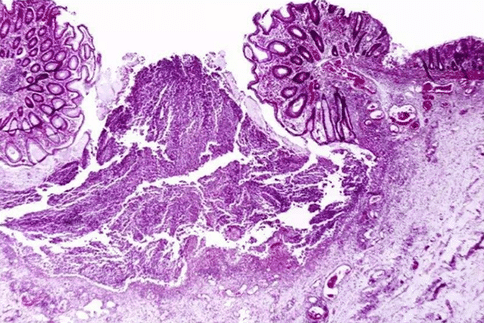

什么是組織活檢?

組織活檢,全稱活體組織檢查(biopsy),也叫做外科病理學(xué)檢查,指的是從患者體內(nèi)切取、鉗取或穿刺等方式取出病變組織,以便進(jìn)行病理學(xué)檢查的技能。這項(xiàng)技能是診斷病理學(xué)中非常重要的部分,對(duì)大多數(shù)送檢病例都能做出準(zhǔn)確的組織病理學(xué)診斷。